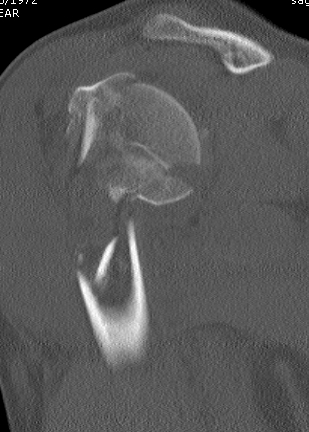

proximal humerus fracture Background ORIF with locking plate Arthroplasty Greater tuberosity fractures Lesser tuberosity fractures / avulsions Book traversal links for Proximal humerus fractures ‹ Pectoralis Major Tears Up Background ›